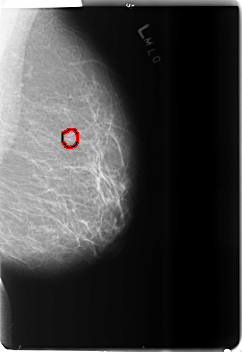

B_3494_1.LEFT_MLO

LEFT_MLO LINES 5968 PIXELS_PER_LINE 4112 BITS_PER_PIXEL 12 RESOLUTION 50 OVERLAY

FILE: B_3494_1.LEFT_MLO.OVERLAY

TOTAL_ABNORMALITIES 1

ABNORMALITY 1

LESION_TYPE CALCIFICATION TYPE PLEOMORPHIC DISTRIBUTION CLUSTERED

ASSESSMENT 4

SUBTLETY 3

PATHOLOGY BENIGN

TOTAL_OUTLINES 1

BOUNDARY